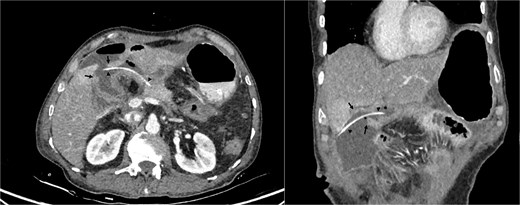

On examination, patient had grossly normal vital parameters with body mass index (BMI) of 18.84 kg/m2 and Eastern Cooperative Oncology Group performance status grade 2. Abdomen was scaphoid with no features of ascites or jaundice. Patient’s hematological and biochemical parameters were within normal limits with Hb 11.2 gm/dl, serum albumin 3.52 gm/dl, carcinoembryonic antigen (CEA) 0.68 ng/ml, carbohydrate antigen (CA) 19.9–4.31 U/ml. Contrast enhanced computed tomography (CECT) abdomen and pelvis revealed heterogeneously enhancing asymmetrical wall thickening of second part of duodenum causing luminal narrowing with dilatation of first part of duodenum and stomach, dilated common bile duct (CBD) of 10.6 mm diameter with dilated intrahepatic biliary radicals and pancreatic duct diameter of 3 mm. On endoscopy, stomach was distended and filled with food particles with non-negotiable stricture at second part of duodenum. Endoscopic biopsy from the lesion revealed moderately differentiated adenocarcinoma. Patient was initially managed with intra-venous fluids and NG decompression of stomach with parenteral nutritional support. After proper optimization, he underwent pylorus resecting PD with findings of hard mass at peri-ampullary region with soft pancreas and main pancreatic duct (MPD) diameter of 3 mm. Reconstruction was performed using the Child’s technique with modified Blumgart PJ and placement of trans-anastomotic stent (5F infant feeding tube; 15 cm length) with two closed suction abdominal drains (Jackson-Pratt drains) in peri-pancreatic and subhepatic spaces. Patient had normal post-operative course and was tolerating semi-solid diet orally. He developed grade A POPF (Day 3 and Day 5 drain fluid amylase were 1276 and 2307 U/L, respectively) with no change in clinical course till 5th post-operative day (POD). On POD 6, he developed tachycardia and epigastric tenderness with localized guarding and high output bilious drainage along with bilious discharge from wound. CECT abdomen revealed perforation of jejunal segment between PJ and hepaticojejunostomy (HJ) with part of the stent in the localized intra-peritoneal collection (Fig. 1).

Cross-sectional image of jejunum perforation (black arrows) and transanastomotic pancreaticojejunostomy stent (black arrow heads).